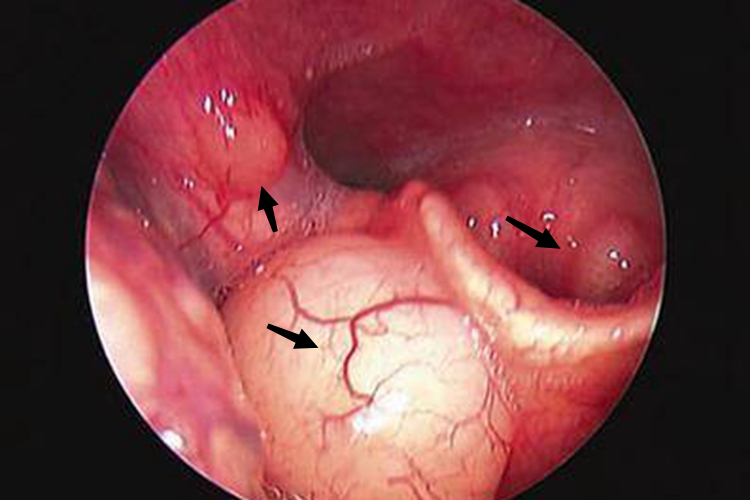

- 咽喉红肿:喉头水肿时,咽喉部的黏膜会出现红肿现象,这是炎症反应的典型表现。红肿的黏膜可能伴随有分泌物增多,进一步加重咽喉不适感。

- 呼吸困难:随着喉头水肿的加重,患者可能会出现呼吸困难的症状。这是因为喉部肿胀导致气道狭窄,影响气体交换。在严重的情况下,患者可能出现窒息等危及生命的症状。